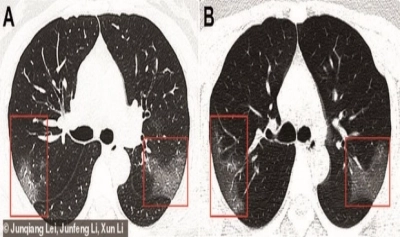

În cele două radiografii, făcute la 3 zile distanță, se pot observa cu ușurință zonele albe care se extind, în ciuda tratamentului primit la spital.

Imaginile au fost prezentate de un grup de cercetători de la The First Hospital of Lanzhou University, în revista Radiology.